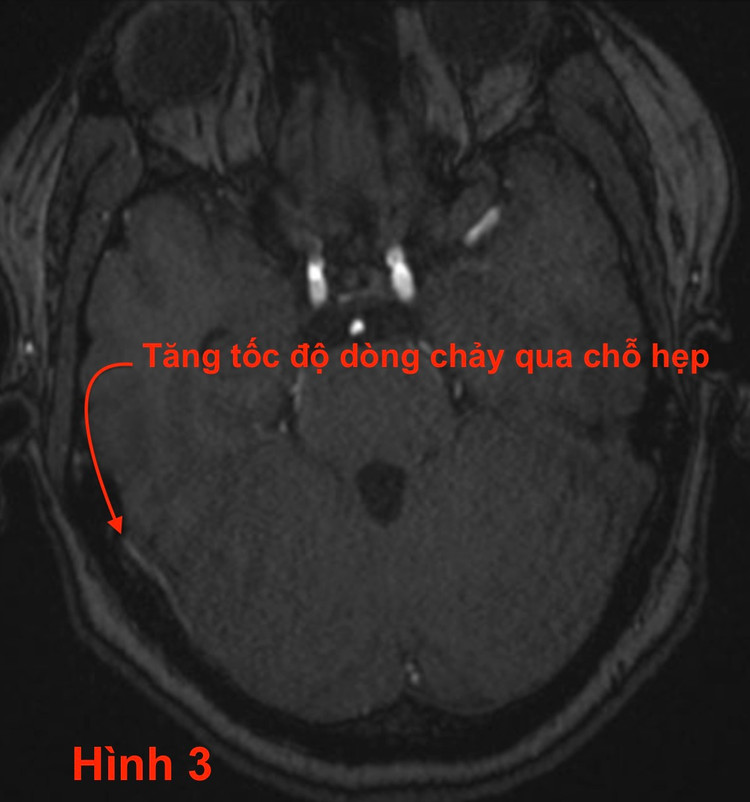

- Chẩn đoán xác định dựa vào CTA và MRI (chứ không phải DSA): Phim chụp CT có tiêm thuốc thấy hẹp xoang tĩnh mạch ngang bên phải (hình 2). Vị trí hẹp mạch này có tốc độ dòng chảy cao hiện hình trên xung TOF3D của MRI (hình 3).